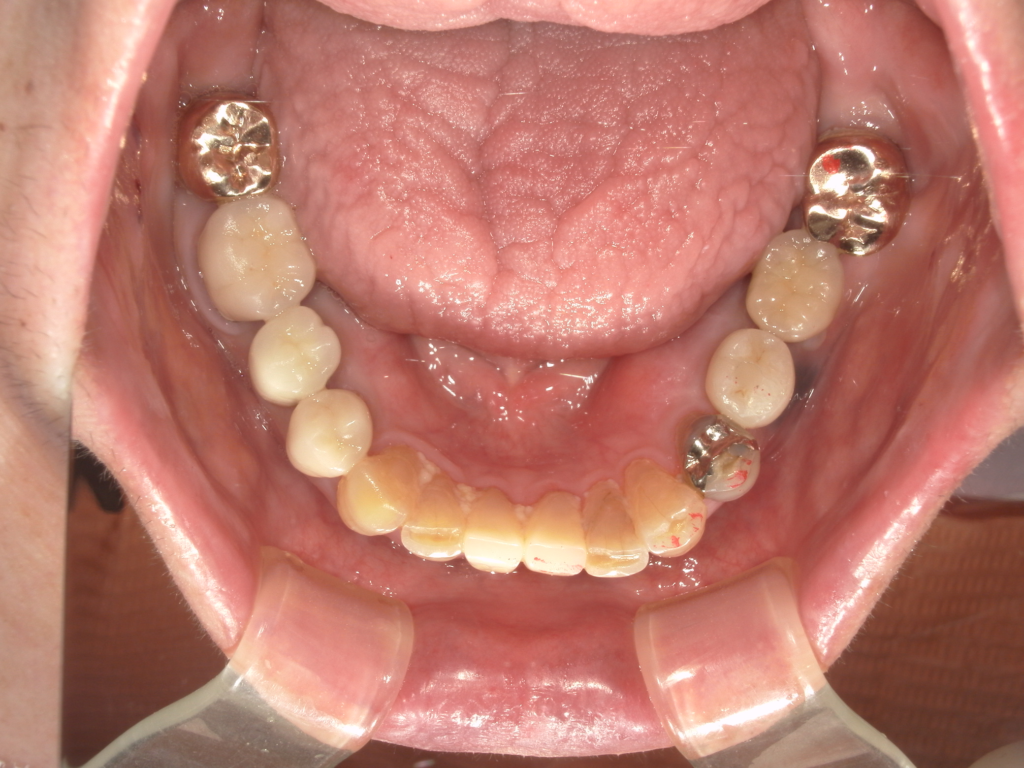

Y様インプラント実例 #44

左の上下の奥歯をインプラントで治療しています。

左下の奥歯は歯を抜くのと同時にインプラントの埋め込みを行っています。

被せものは上下、セラミックスで作っています。

治療前

治療後